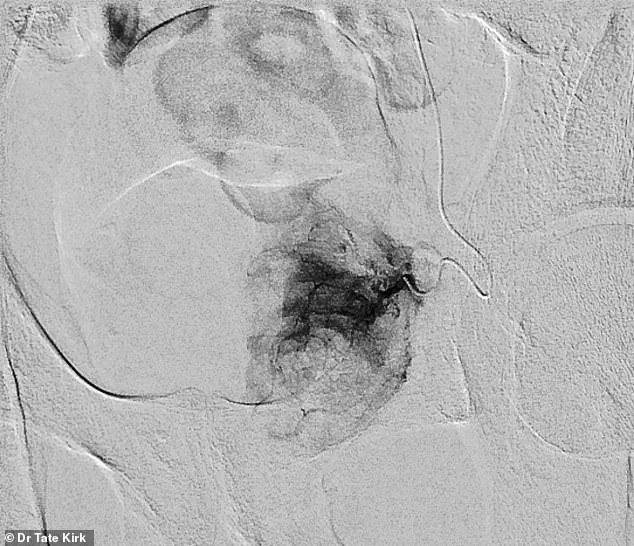

Pre-embolization imaging reveals the catheter's placement within the artery feeding the left half of an enlarged prostate.

Once the embolic material is deployed, post-embolization imaging confirms the absence of blood flow to the prostate tissue from the treated artery.

This targeted approach reduces the risk of collateral damage to surrounding tissues, a critical advantage in preserving sexual function—a concern that has historically plagued other treatments.